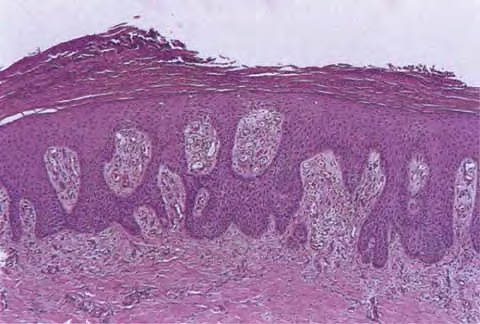

exocytosis of neutrophils, they may aggregate in the uppermost portion of the spinous layer to form small spongiform pustules of Kogoj. Lymphocytes remain confined to the lower epidermis, which, as more and more mitoses occur, becomes increasingly hyperplastic. The epidermal changes are at first focal, but later become confluent, leading clinically to plaques. In the fully developed lesions of psoriasis, as best seen at the margin of enlarging plaques, the histologic picture is characterized by (a) acanthosis with regular elongation of the rete ridges with thickening in their lower portion; (b) thinning of the suprapapillary epidermis with the occasional presence of small spongiform pustules; (c) pallor of the upper layers of the epidermis; (d) diminished to absent granular layer; (e) confluent parakeratosis; (f) the presence of Munro microabscesses; (g) elongation and edema of the dermal papillae; and (h) dilated and tortuous capillaries . |

The rete ridges show considerable elongation and extend downward to a uniform level, resulting in regular acanthosis . They are often slender in their upper portion but |

show thickening ("clubbing") in their lower portion. Not infrequently, adjacent rete ridges seem to coalesce at their bases due to tangential sectioning. Usually, intercellular and intracellular edema is absent in the rete ridges, and keratinocytes located well above the basal layer show deep basophilia. In addition, mitoses are not limited to the basal layer as in normal skin but are also seen above the basal layer. This, together with a considerable lengthening of the basal cell layer due to elongation of the rete ridges, results in a marked increase in the number of mitoses. This increase has been calculated to be 27 times the number of mitoses in uninvolved skin . |

The suprapapillary epidermis appears relatively thin in comparison with the markedly elongated rete ridges, and the cells in the upper layers of the epidermis may appear enlarged and pale stained as a result of intracellular edema and hypogranulosis. Keratinocytes beneath the parakeratotic cornified layer may be intermingled with neutrophils . The histologic picture is then that of a small spongiform pustule of Kogoj . Although it is only a micropustule, it is nevertheless of the same type as the much larger macropustules seen in pustular psoriasis. Such a spongiform pustule, highly diagnostic for psoriasis and its variants, shows aggregates of neutrophils within the interstices of a spongelike network formed by degenerated and thinned epidermal cells |

Munro microabscesses are located within the parakeratotic areas of the cornified layer . They consist of accumulations of neutrophils and pyknotic nuclei of neutrophils that have migrated there from capillaries in the papillae through the suprapapillary epidermis. As a rule, Munro microabscesses are easily found in early lesions but are few in number or absent in longstanding lesions . The dermal papillae, in accordance with the elongation and basal thickening of the rete ridges, are elongated and club shaped. They show edema, and the capillaries within them appear dilated and tortuous. A relatively mild inflammatory infiltrate is present in the upper dermis and the papillae. It consists of lymphocytes, except in early lesions, in which neutrophils are also present in the upper portion of the papillae . |